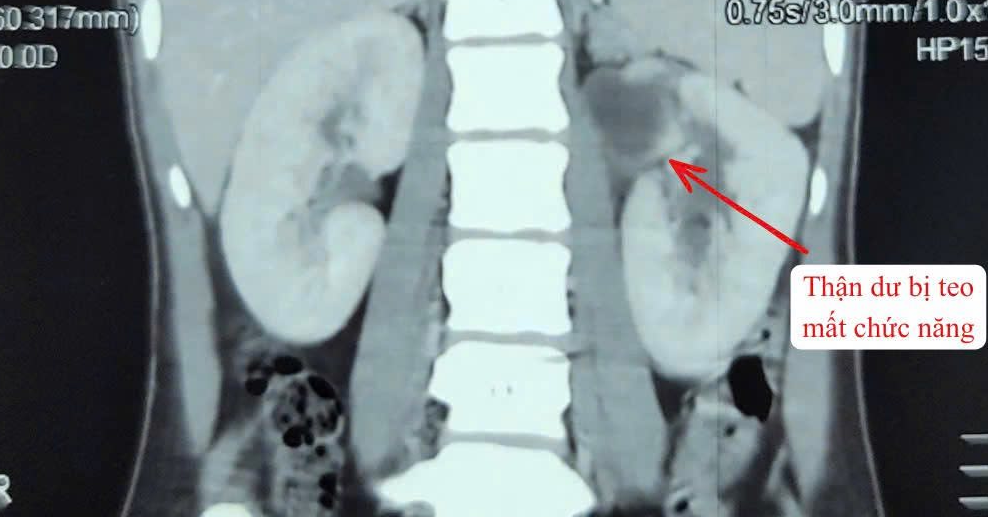

A 22-year-old woman has been successfully treated for an exceptionally rare congenital urinary anomaly involving three kidneys, doctors at Quang Nam Regional General Hospital announced on March 27.